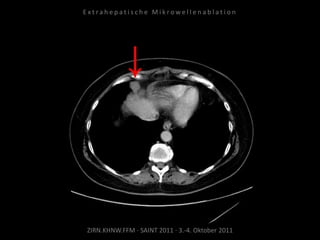

Bildgebung vor MWA:

CT 09.09.2010

Situation:

Tumorerkrankung mit ausgedehnter

Metastasierung. Schmerzsymptomatik

durch Metastasen am Truncus coeliacus.

Ziel:

Druckreduzierung durch Reduzierung

der Tumorlast, thermische Reduktion

der Schmerzfasern am Truncus, dadurch

Reduzierung der hierdurch bedingten

Beschwerden. Kein kurativer Ansatz.

Indikation zur MWA:

Aufgrund der gefäßnahen Lage stellt die

MWA mit ihrer der exakten

Positionierbarkeit und dem exakt

definierten Ablationsvolumen die

Methode der Wahl dar.

Ablation am 07.10.2010:

Je eine Nadelposition von links und

von rechts.